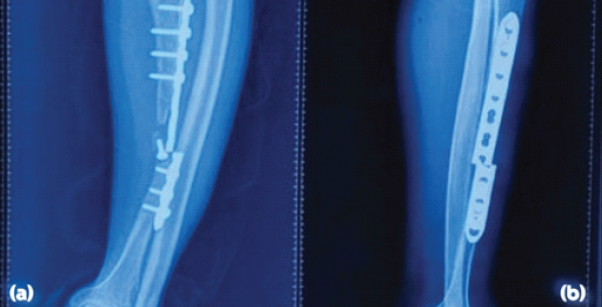

A non-union of the tibia with bone loss was observed, accompanied by a broken 4.5 mm narrow limited contact dynamic compression plate and multiple screw loosening (Fig. 2).

Figure 2: X-rays of left polio deformed tibia non-union with broken implant in situ, anteroposterior (a) and lateral (b) views.